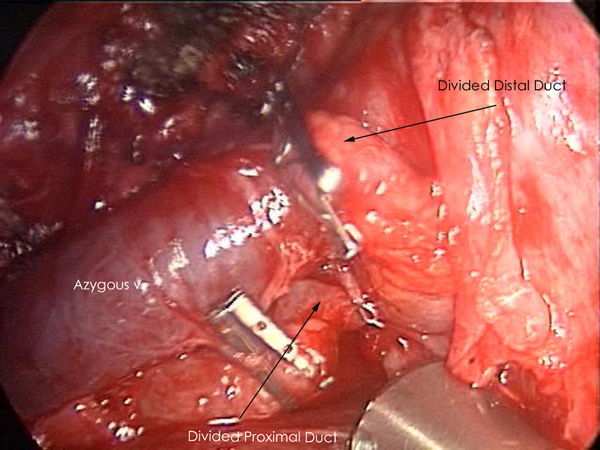

Exploration of this area bluntly will reveal the thoracic duct as a thin tubular structure with occasional peristalsis (Video 5). Once a sufficient length of duct is isolated it is doubly clipped using 5 or 10mm clips depending on the size of the duct and is divided (Figures 4-6). Transection with a linear cutting stapler with a vascular load (30mm length, 2.0mm staple height) works just as well (Video 6). The stapler or clip applier can be introduced through the working incision or the incision used for retraction of the diaphragm. If an adequate length of the duct can be isolated, a portion can be excised and sent for frozen section to confirm its identity.

| Figure 4: Thoracic Duct isolation. | Figure 5: Thoracic Duct Ligation. | Figure 6: Thoracic Duct Divided. |